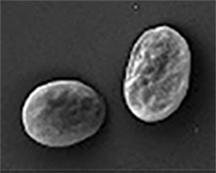

Researchers have since learned that the receptor P2Y12 communicates with a small protein called Rap1, which is like a cellular switch. In platelets, this switch is typically off, which keeps platelets in a non-sticky state. In this quiet state, the 2.5 trillion platelets can patrol blood vessels and arteries without sticking to the endothelium - or inside wall - of, say, a coronary artery. If there's a problem in the endothelium, the Rap1 switch is flipped and platelets morph into super sticky cells that clot fast to keep blood from gushing into tissue.

His team knocked out Rasa3 in mice to show that the offspring had no platelets and could not survive. The researchers then used mice from The Jackson Laboratory to study platelets in mice with a Rasa3 mutation. These mice had 3 to 5 percent of the typical platelet count. Bergmeier's team found that the rest of the platelets were being activated and cleared from circulation.